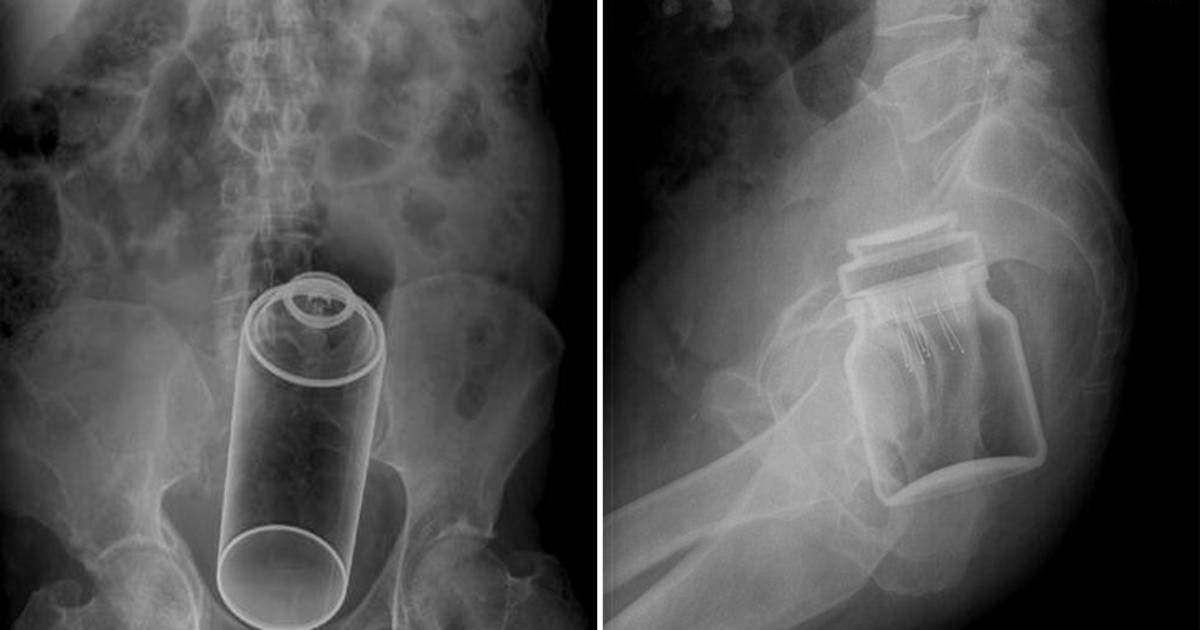

Radiopaedia.org tiene una sección especial de objetos encontrados en dicha zona del cuerpo, la cual es editada por dos doctores australianos. En ella se muestran radiografías de infortunadas personas que terminaron en salas de emergencia con objetos extraños dentro de ellos.

Entre los objetos encontrados dentro están botellas, vegetales, dildos, una cola de cerdo congelada, desodorantes, un frasco de café instantáneo o paquetes con droga.

La mayoría de los objetos llegan a esos lugares como resultado de algún episodio sexual que terminó muy mal y la mayoría son removidos mediante extracción o generando presión en el abdomen.